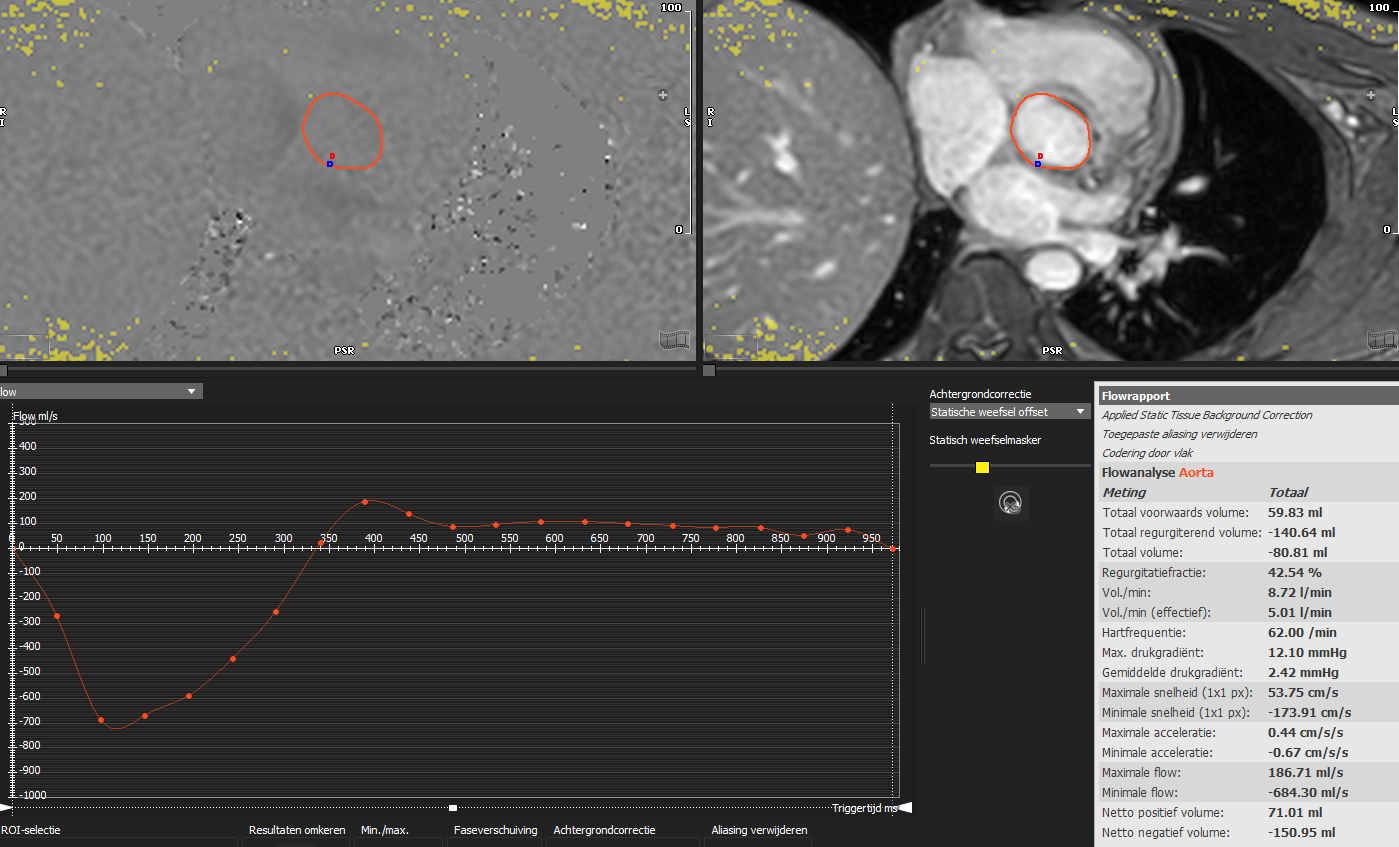

Fig. 4.

Fig. 4.Aortic flow quantification on cardiac magnetic resonance phase contrast imaging. Flow quantification in the ascending aorta allows for quantification of forward volume, regurgitant volume and regurgitant fraction irrespective of the presence of other combined valvulopathies. In the image, a patient with both aortic and mitral regurgitation and left ventricle dilation underwent cardiac magnetic resonance in order to determine the severity of the main lesion, being the aortic regurgitation. The analysis revealed a regurgitant fraction of 42%, compatible with a significant aortic regurgitation.